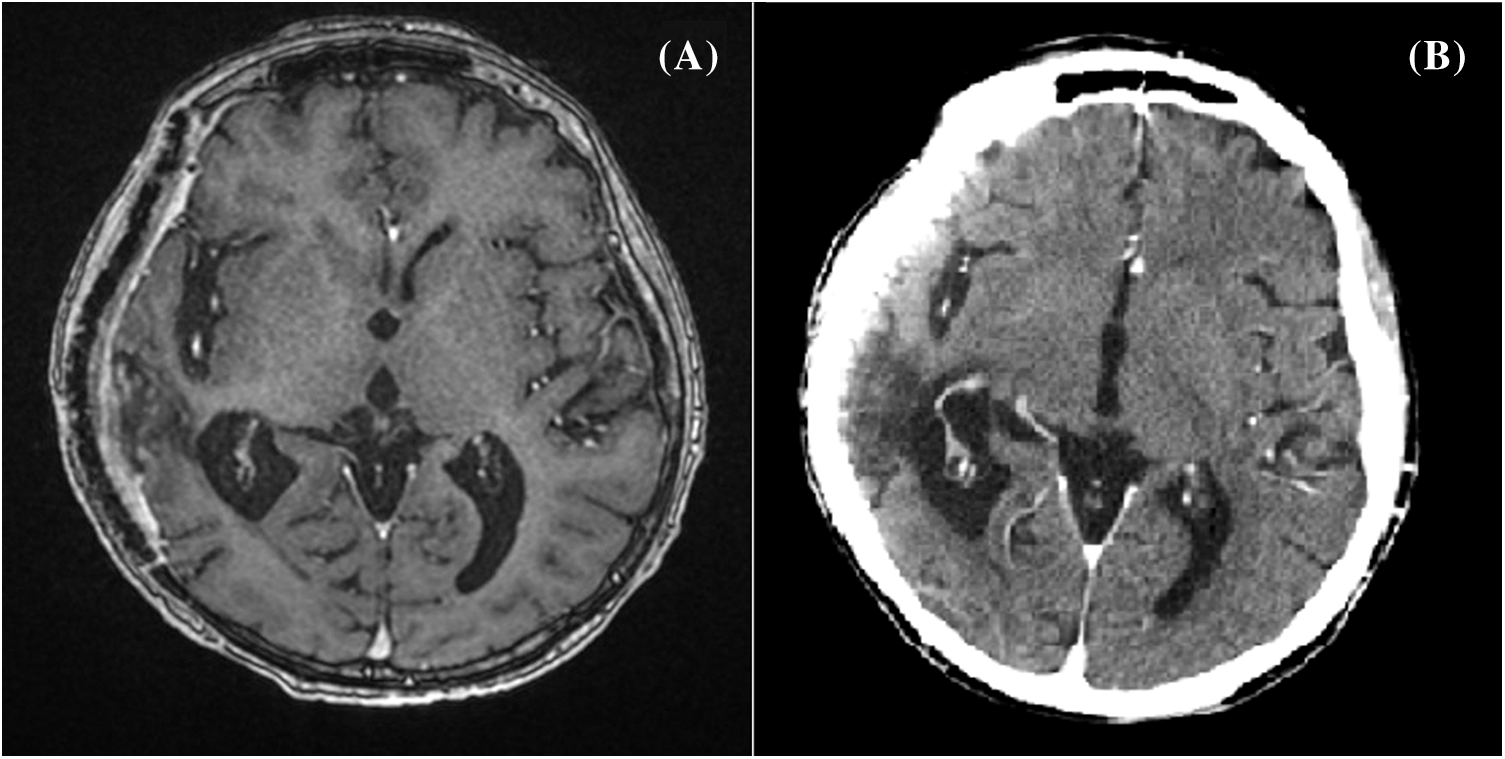

A whole body 18-FDG PET/CT scan was subsequently performed, revealing no tracer uptake (Figs. 2A, 2B). Postoperative brain CT and MRI scan showed a complete removal of the lesion (Figs. 3A, 3B). The patient progressively improved, most notably after performing hydroxyapatite cranioplasty (Fig. 4). The patient was discharged on postoperative day 20 and transferred to the radiation oncology unit for the adjuvant treatments.

Figure 2: Whole body (A) and cerebral (B) 18-FDG PET/CT scan showing no tracer uptake

Figure 3: Postoperative brain contrast-enhanced T1-contrast MRI (A) and head CT scan (B) showing a complete removal of the lesion